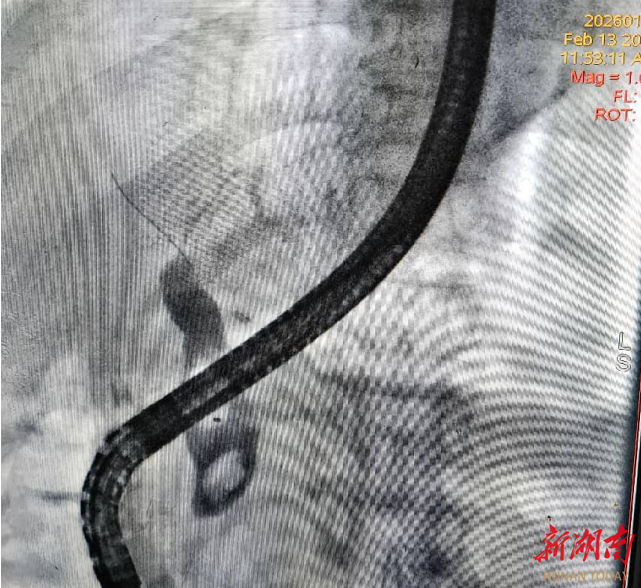

怀化市中心医院靖州院区成功为肝移植术后患者实施ERCP取石术